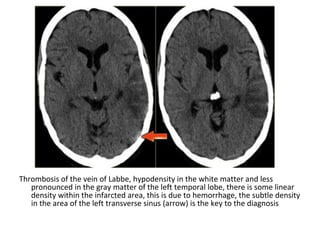

3-Unilateral Infarct :

-Thrombosis of the transverse sinus and / or

vein of Labbe may result in an infarct involving

the grey and white matter of the temporal

lobe in a non-arterial distribution

-Midline venous occlusion may also present with

unilateral infarcts

Thrombosis of the vein of Labbe, hypodensity in the white matter and less

pronounced in the gray matter of the left temporal lobe, there is some linear

density within the infarcted area, this is due to hemorrhage, the subtle density

in the area of the left transverse sinus (arrow) is the key to the diagnosis

There is a combination of vasogenic edema (red arrow) , cytotoxic edema and

hemorrhage (blue arrow) , these findings and the location in the temporal lobe

should make you think of venous infarction due to thrombosis of the vein of Labbe

(Hemorrhagic venous infarct in Labbe territory)